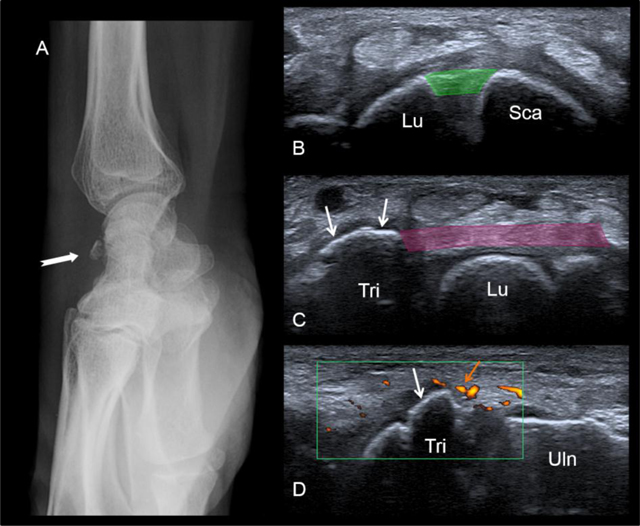

Figure 10

Bony avulsion of the dorsal sling (triquetral insertion). A fracture is seen on the lateral radiograph (A). At the US examination, the dorsal band of the scapholunate ligament (in green) is normal (B). In contrast US shows the bony avulsion of the triquetral insertion of the dorsal radiolunotriquetral ligament (white arrows). See the soft-tissue hyperemia surrounding the avulsion on the long-axis view (orange arrow). Lu = lunate, Sca = scaphoid, Tri = triquetrum, Uln = ulna.